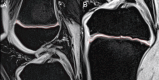

Methods: The study included 31 healthy children (17 boys, 14 girls) under evaluation for growth retardation. Height, weight, bone age, insulin like growth factor-1 (IGF-1), and insulin like growth factor binding protein 3 (IGF-BP3) were measured at baseline and after 6 months. In addition, the diameter, thickness, and volume of the femoral and tibial growth plates were measured using magnetic resonance imaging.

Results: The mean bone age in boys and girls was 11.7 and 10.7 years, respectively. In boys, height (z score) (-0.2 vs. 0.0), weight (z score) (0.8 vs. 1.1), body mass index (BMI) (z score) (1.27 vs. 1.5), IGF-1 (ng/mL) (343.6 vs. 501.8), and IGF-BP3 (ng/mL) (5,088.5 vs. 5,620.0) were significantly higher after 6 months. In girls, height (z score) (-1.0 vs. -0.7), weight (z score) (-0.5 vs. 0.1), BMI (z score) (-0.02 vs. 0.3), IGF-1 (ng/mL) (329.3 vs. 524.6), and IGF-BP3 (ng/mL) (4,644.4 vs. 5,593.6) were also significantly higher after 6 months. In both sexes, the mean diameter and volume of the femoral and tibial growth plates were significantly increased 6 months later.